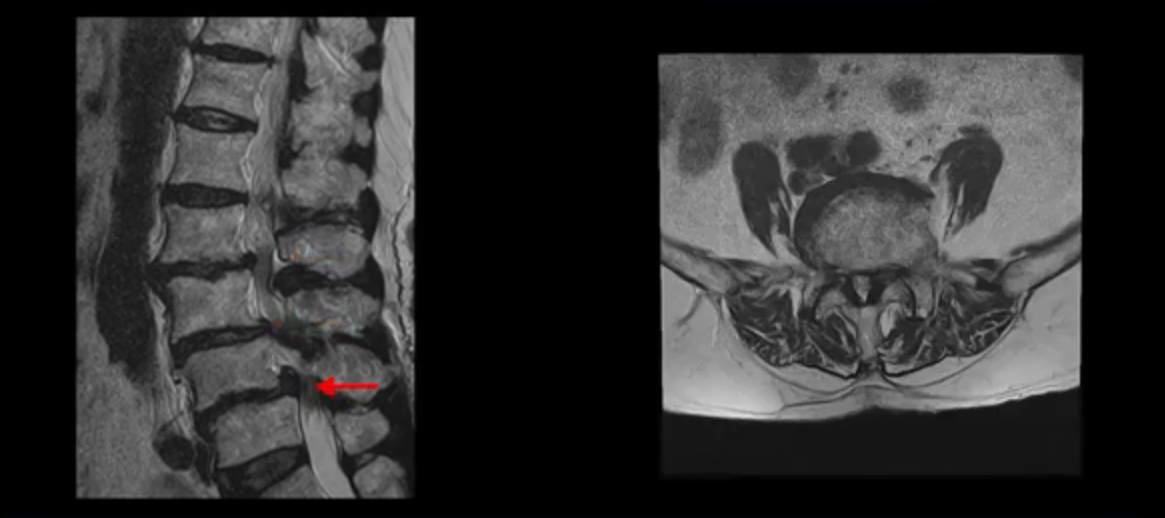

이 환자분 MRI를 보면서 더 자세히 설명 드리겠습니다. 이분은 허리의 다섯 마디가 다 안 좋은 환자분입니다. 84세 고령의 나이에 이렇게 여러 마디가 안 좋으면 대학병원에서도 수술이 어렵다는 얘기를 듣는 경우가 많습니다. 또 수술을 하더라도 결과가 안 좋을 수 있다는 얘기를 들을 가능성이 높습니다.

보시다시피 허리 다섯 마디 전부가 다 퇴행되어 있고,

두 마디에 전방전위증이 있고,

2번 3번,

3번 4번,

4번 5번에 중심성 협착이 심하고

거의 모든 추간공 즉, 신경가지가 좌우로 빠져나가는 구멍이 다 좁아져 있습니다.